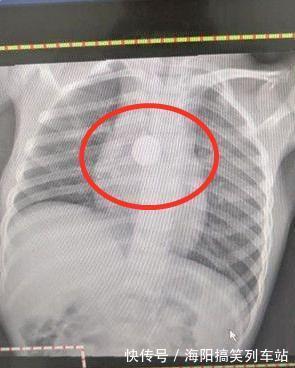

位于澳洲墨尔本的琪拉女士万万没有想到自己5岁的女儿这段时间竟然开始暴瘦了,以往孩子从来都没有出现过这样的情况,毕竟孩子一直都很健康,这到底是怎么回事呢?为了查证原因,李女士带着女儿去医院做了一个检查。不过就在做x光的时候,医生有点懵了。孩子的胸前有一个非常明显的圆形的''项链'',可是就在下一刻李女士说出来的话,让医生察觉到了问题所在。

琪拉女士说道''我家孩子没带项链啊。''听到这句话后,医生又看了看小女孩的脖子处,顿时恍然大悟。只见小女孩根本没有戴项链,因此小女孩肯定是因为不小心吞食了什么异物,才会在拍X光的时候拍出个''项链''。

所幸及时发现了问题所在,仔细检查后,医生发现在小女孩的喉咙处卡了一颗纽扣电池。经过手术后,电池也顺利地取了出来,虽然小女孩的喉咙有一些受损,之后几天可能会影响到进食,但所幸没有耽误太久,这颗纽扣电池没有对孩子造成更严重的伤害。